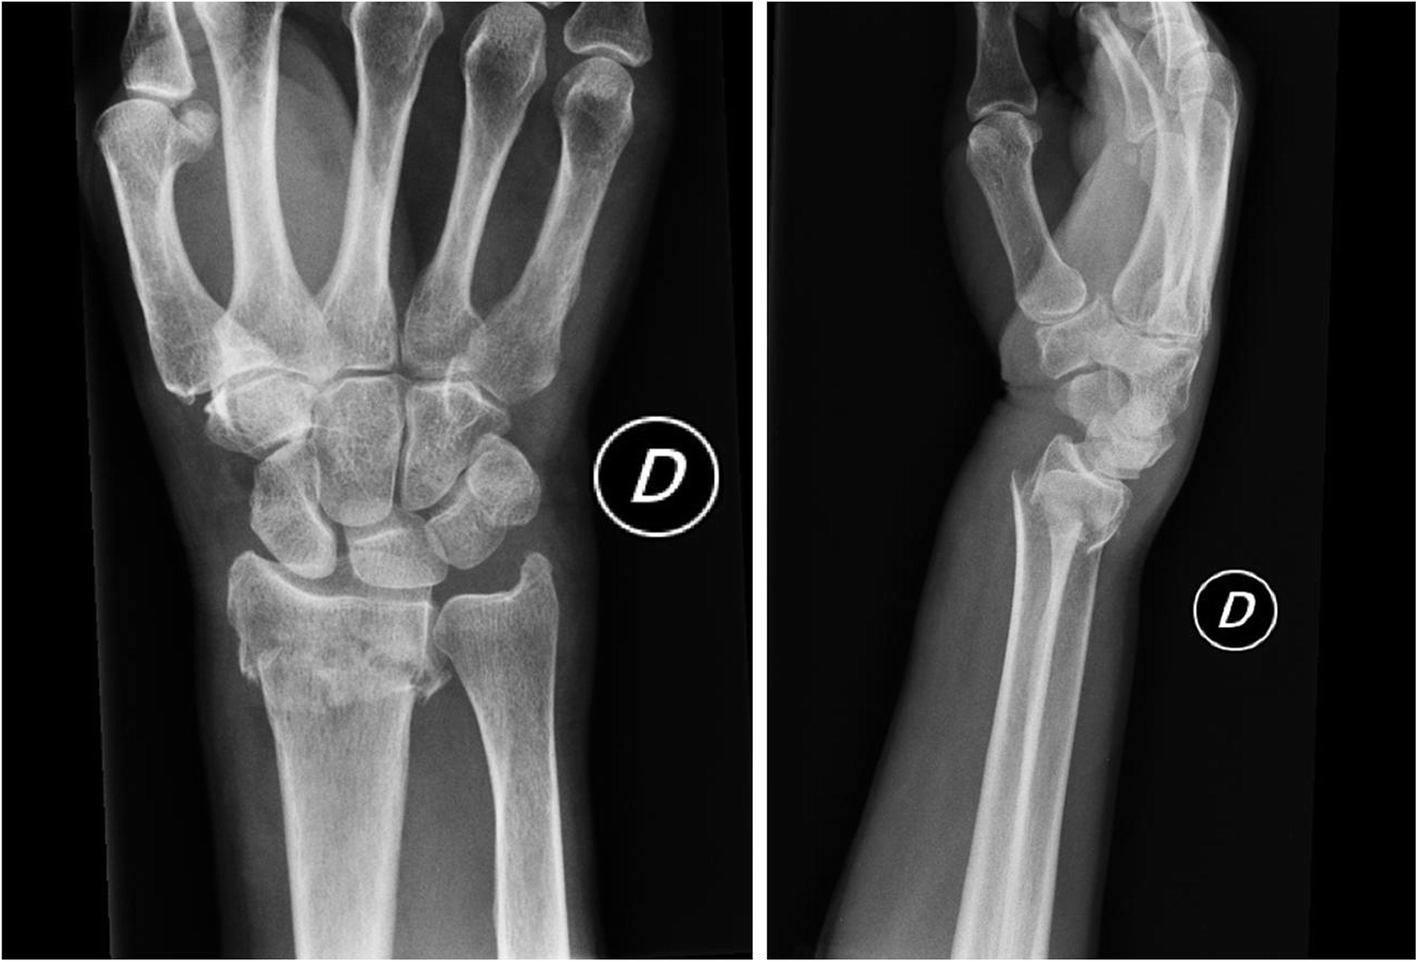

Extra articular distal radius fracture. The decision for a cc or a ps was mostly based on the hospitals protocol and preference of the treating physician. On this image, there is a small coronal fracture in the distal radius, but with minimal displacement. Other ways the distal radius can break include:

A fracture that extends into the wrist joint. Optimal treatment is achieved when the pattern of injury is recognized and its component parts are adequately addressed.

A fracture that extends into the wrist joint.